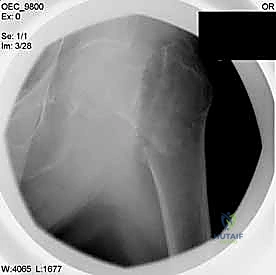

التصوير الطبي المتقدم

- الأشعة السينية (X-rays): هي المعيار الذهبي الأولي. يتم أخذ صور من الأمام للخلف (AP) وصور جانبية (Lateral) للحوض والورك المصاب. تكشف هذه الصور عن موقع الكسر، نوعه (بسيط أم مفتت)، ودرجة الإزاحة.

مجموعة من الصور الإضافية التي توضح مراحل دقيقة من العمل الجراحي المعقد الذي يجريه الأستاذ الدكتور محمد هطيف لضمان أعلى درجات الدقة الميكانيكية الحيوية: